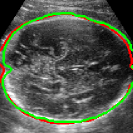

As mentioned in Sec. 3.2, it is crucial for our brain extraction network to work consistently regardless of the orientation of the brain within the US volume. This can be qualitatively observed in Fig. 3, which shows the outline of the brain-extraction prediction and the corresponding ground-truth, in red and green respectively, for six different 3D US volumes. These volumes have been selected to demonstrate the amount of variation between each scan, with the position of the fetus inside the mother as well as the position of the brain in respect to the scan varying drastically from case to case.

As shown in Fig. 3 , the network’s prediction is remarkably close to the ground-truth, regardless of the position of the brain in the volume. It also manages to accurately predict the location of the brain when this is partially obscured either by the cropping or the shape of the ultrasound beam.